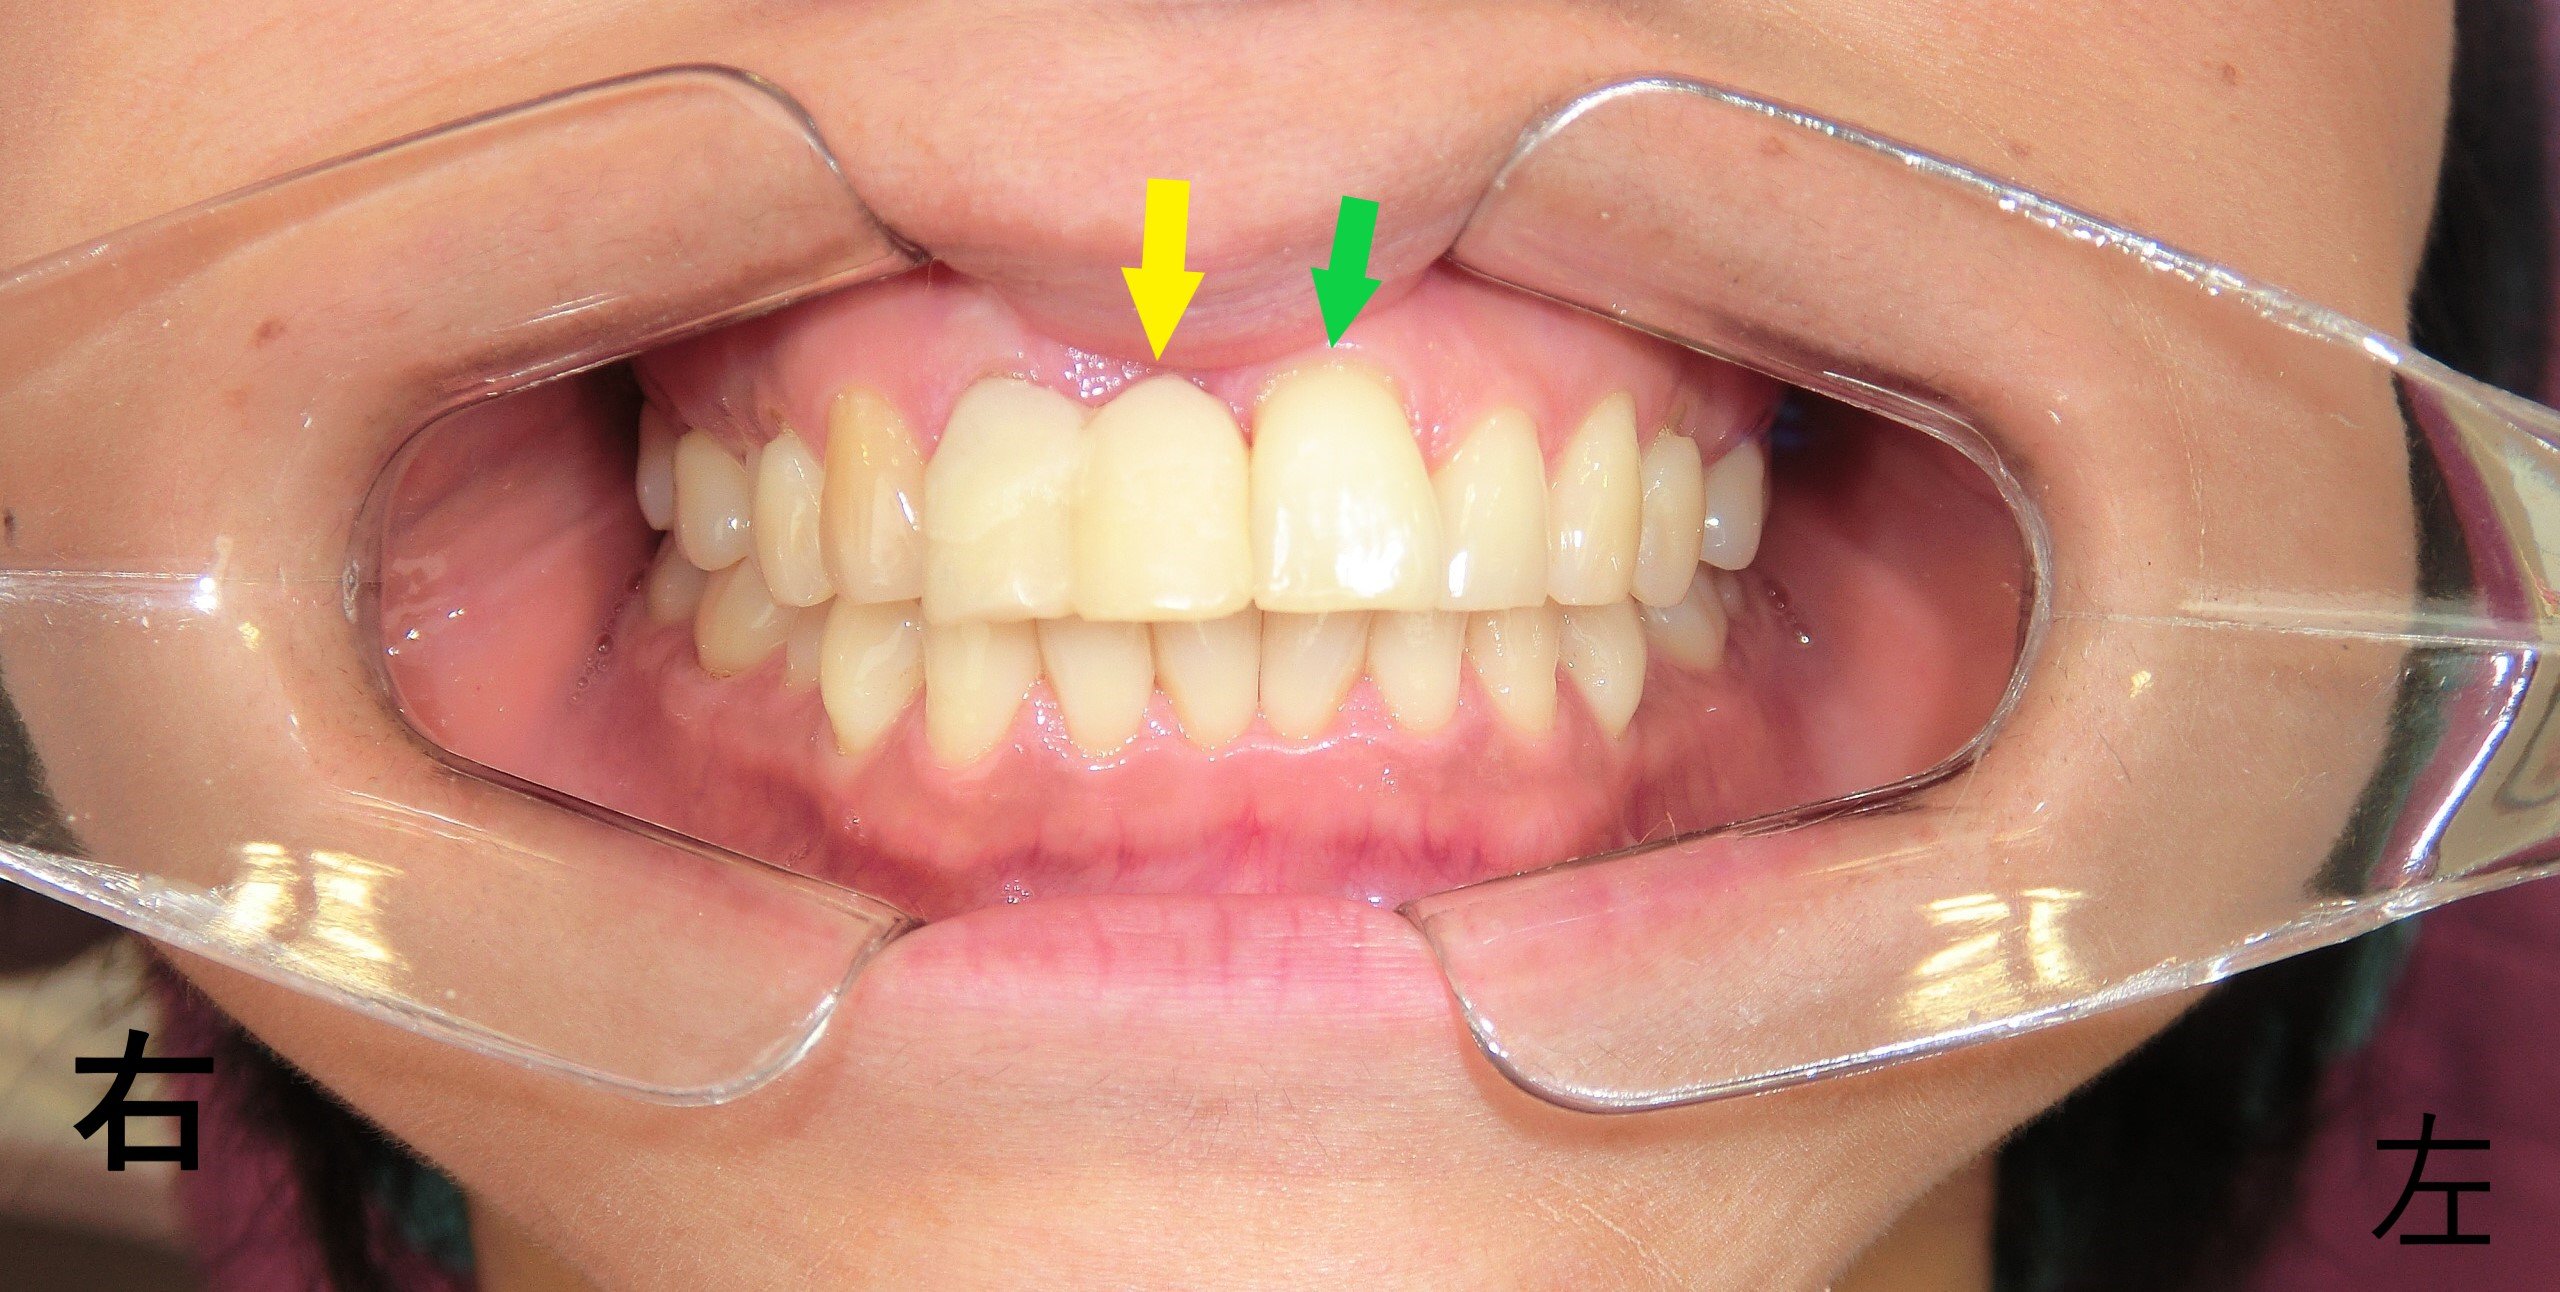

プチ矯正症例40代女性 矯正前

202X年5月、「右上前歯(黄色矢印)の凹みが気になる」という主訴で来院された患者様の症例です。写真をご覧いただくと、右上前歯が左上前歯(緑色矢印)よりも内側に位置して見えるのが確認できます。

しかし、実際には左上前歯が前方に位置しており、それによって右上前歯が凹んで見えている状態でした。